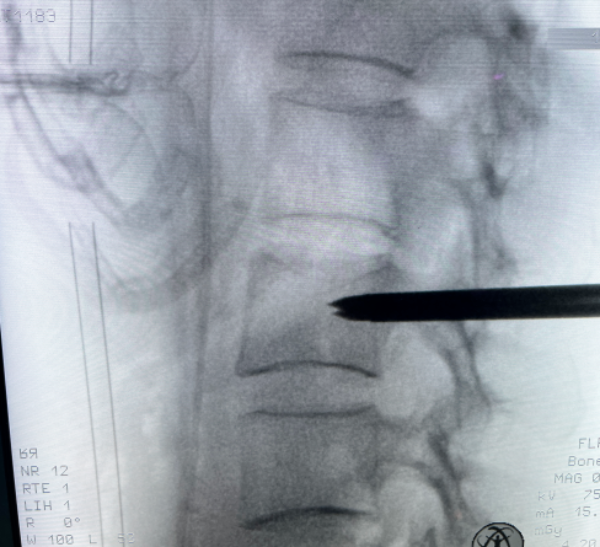

△ 谢翰博士及黄富主治医师行经皮穿刺。

△ 穿刺到达腰2椎体内病灶。